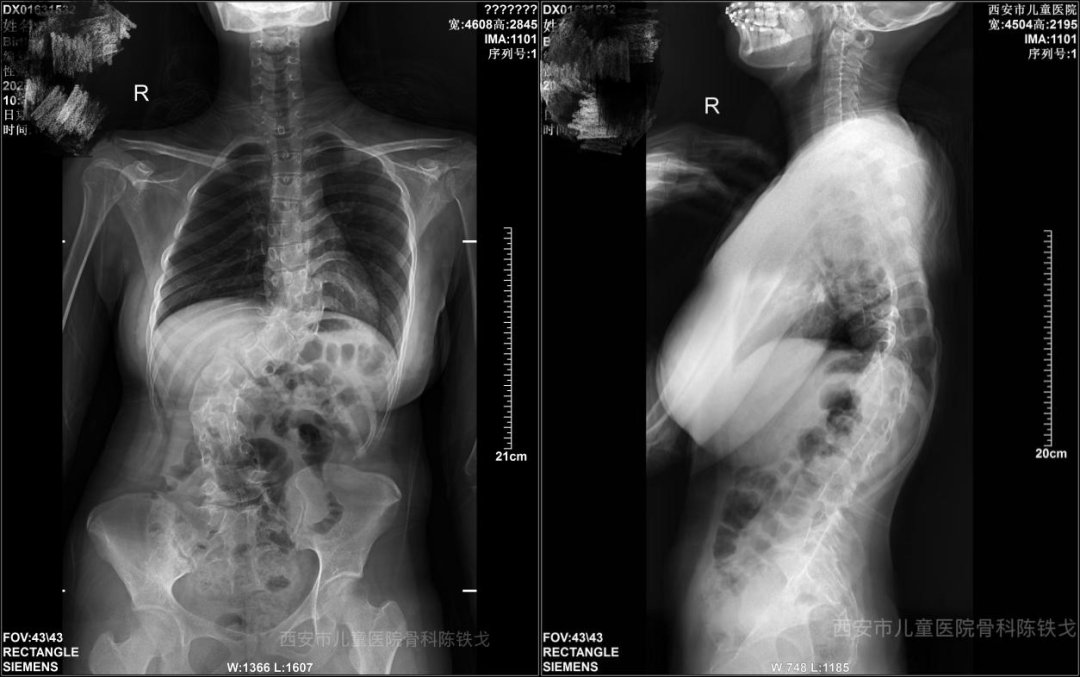

接诊后,骨科团队迅速为小王完成全面影像学评估,结果显示其脊柱存在复杂先天性椎体畸形,侧凸与后凸角度极大,属重度僵硬性畸形。先天性脊柱畸形手术本就如“悬崖走钢丝”,重度畸形更是难上加难,需采用全脊椎截骨等高级技术,而相关文献显示此类手术神经系统并发症发生率达13.6%。小王还合并脊髓纵裂、脊髓栓系,进一步增加手术风险。

借助术前3D打印精准模拟与术中神经电生理实时监测,手术团队以毫米级精度开展胸腰段椎管减压、截骨松解与置钉矫形。7小时的精细操作后,手术顺利完成。术后X光片显示,原本严重扭曲的脊柱被矫正至接近生理角度,矫形效果远超预期,小王的躯干恢复平衡,身高有所增加,受压胸腔容积有效释放。在护理团队精心照料下,他恢复良好,久违的笑容重新绽放。